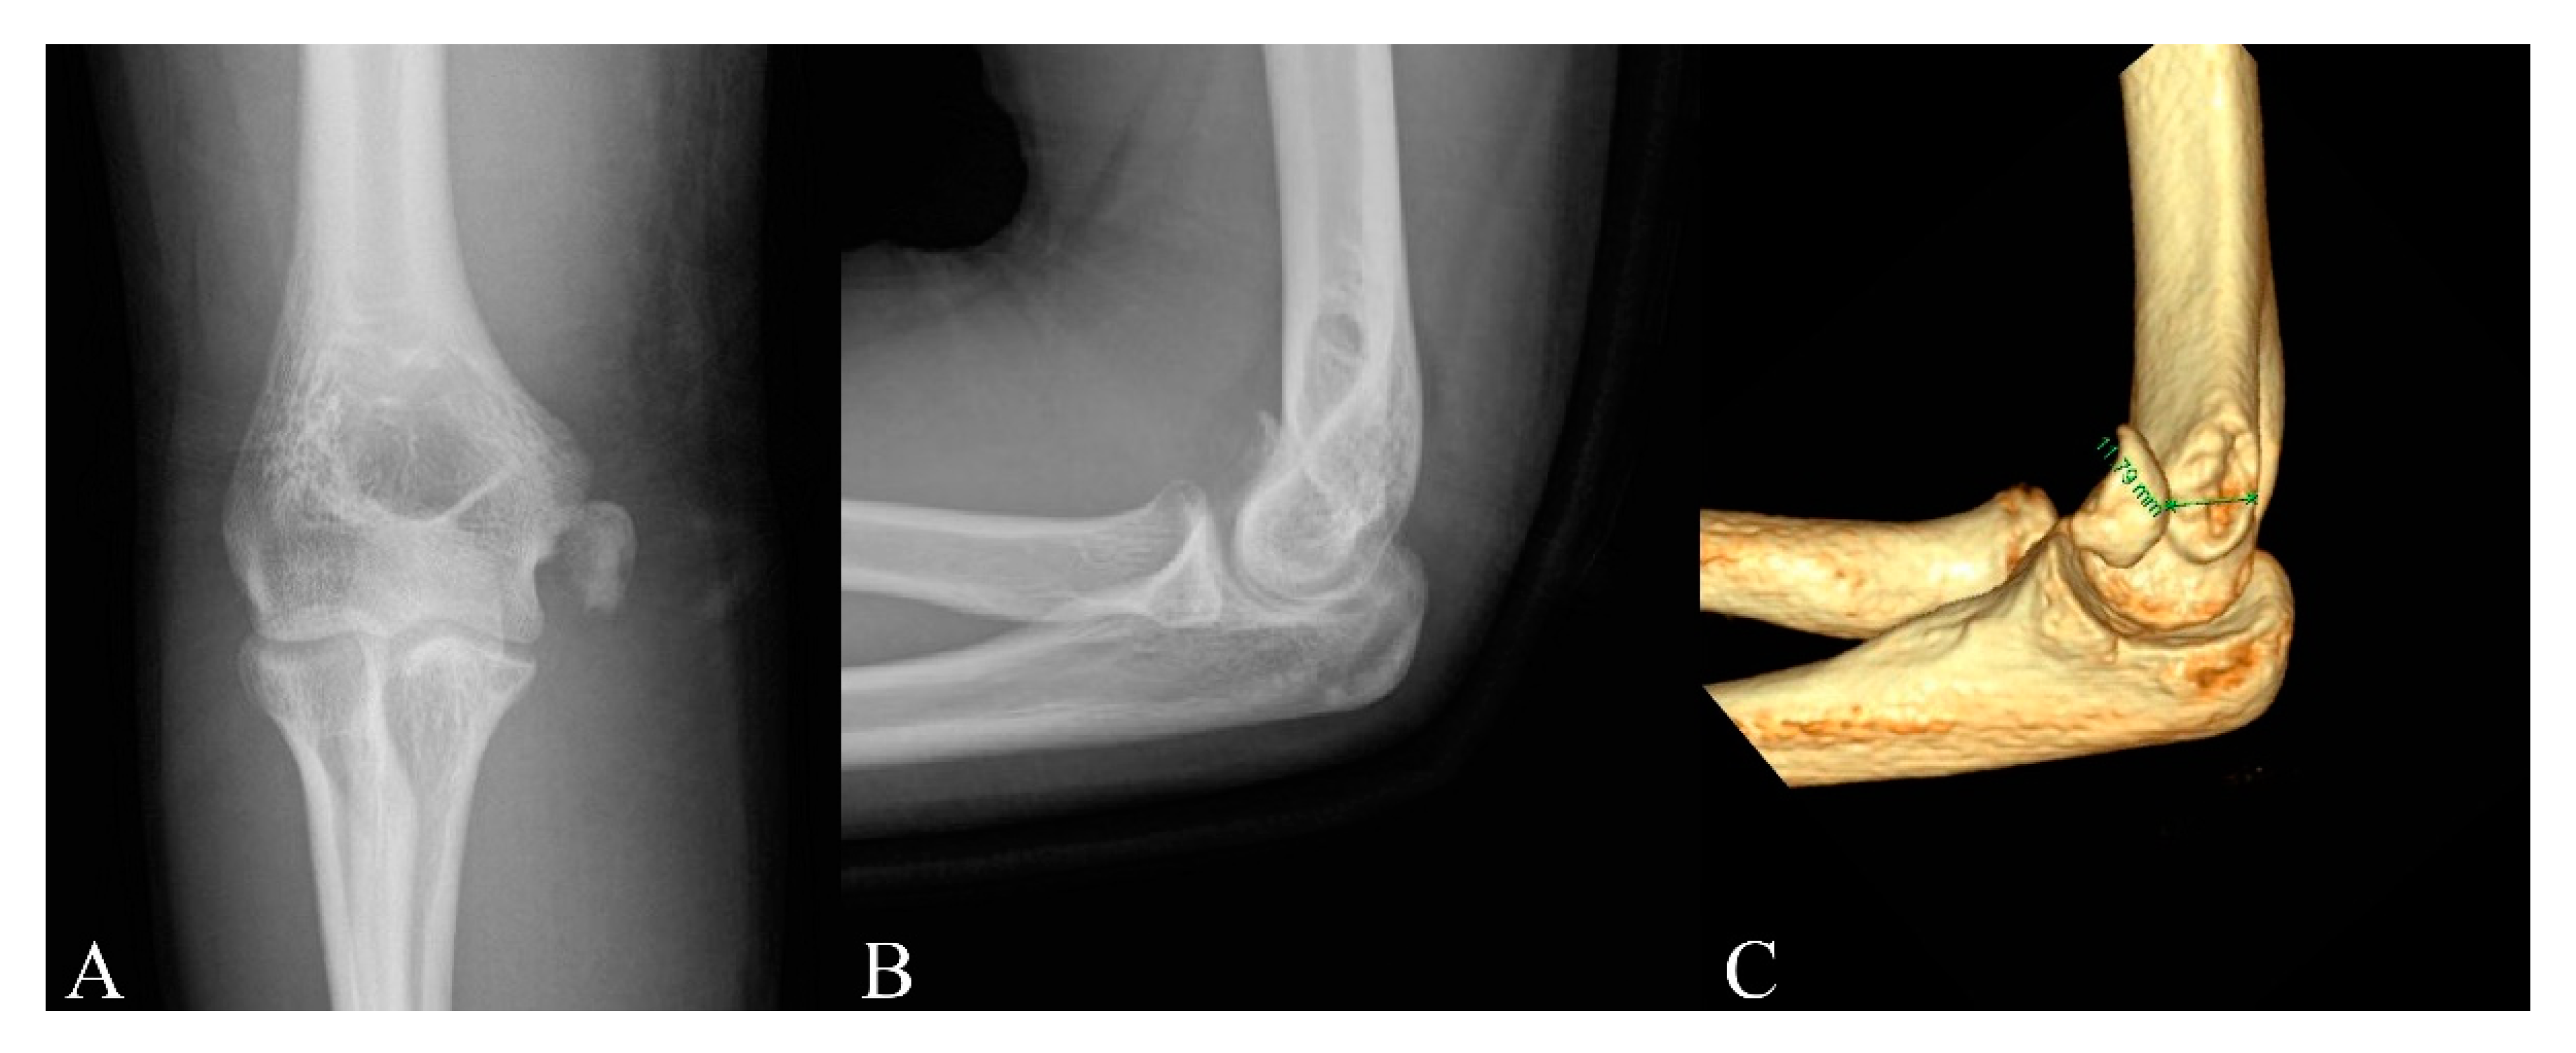

Is Computed Tomography Necessary for Diagnostic Workup in Displaced Pediatric Medial Epicondyle Fractures?

- Edmonds, E.W. How displaced are “nondisplaced” fractures of the medial humeral epicondyle in children? Results of a three-dimensional computed tomography analysis. J. Bone Jt. Surg. Am. Vol. 2010, 92, 2785–2791. [Google Scholar] [CrossRef]

- Onay, T.; Aydemir, A.N.; Okay, E.; Topkar, O.M.; Gulabi, D.; Erol, B. Does computerized tomography change the treatment decision in pediatric medial epicondyle fractures? Acta Orthop. Belg. 2019, 85, 79–85. [Google Scholar] [PubMed]